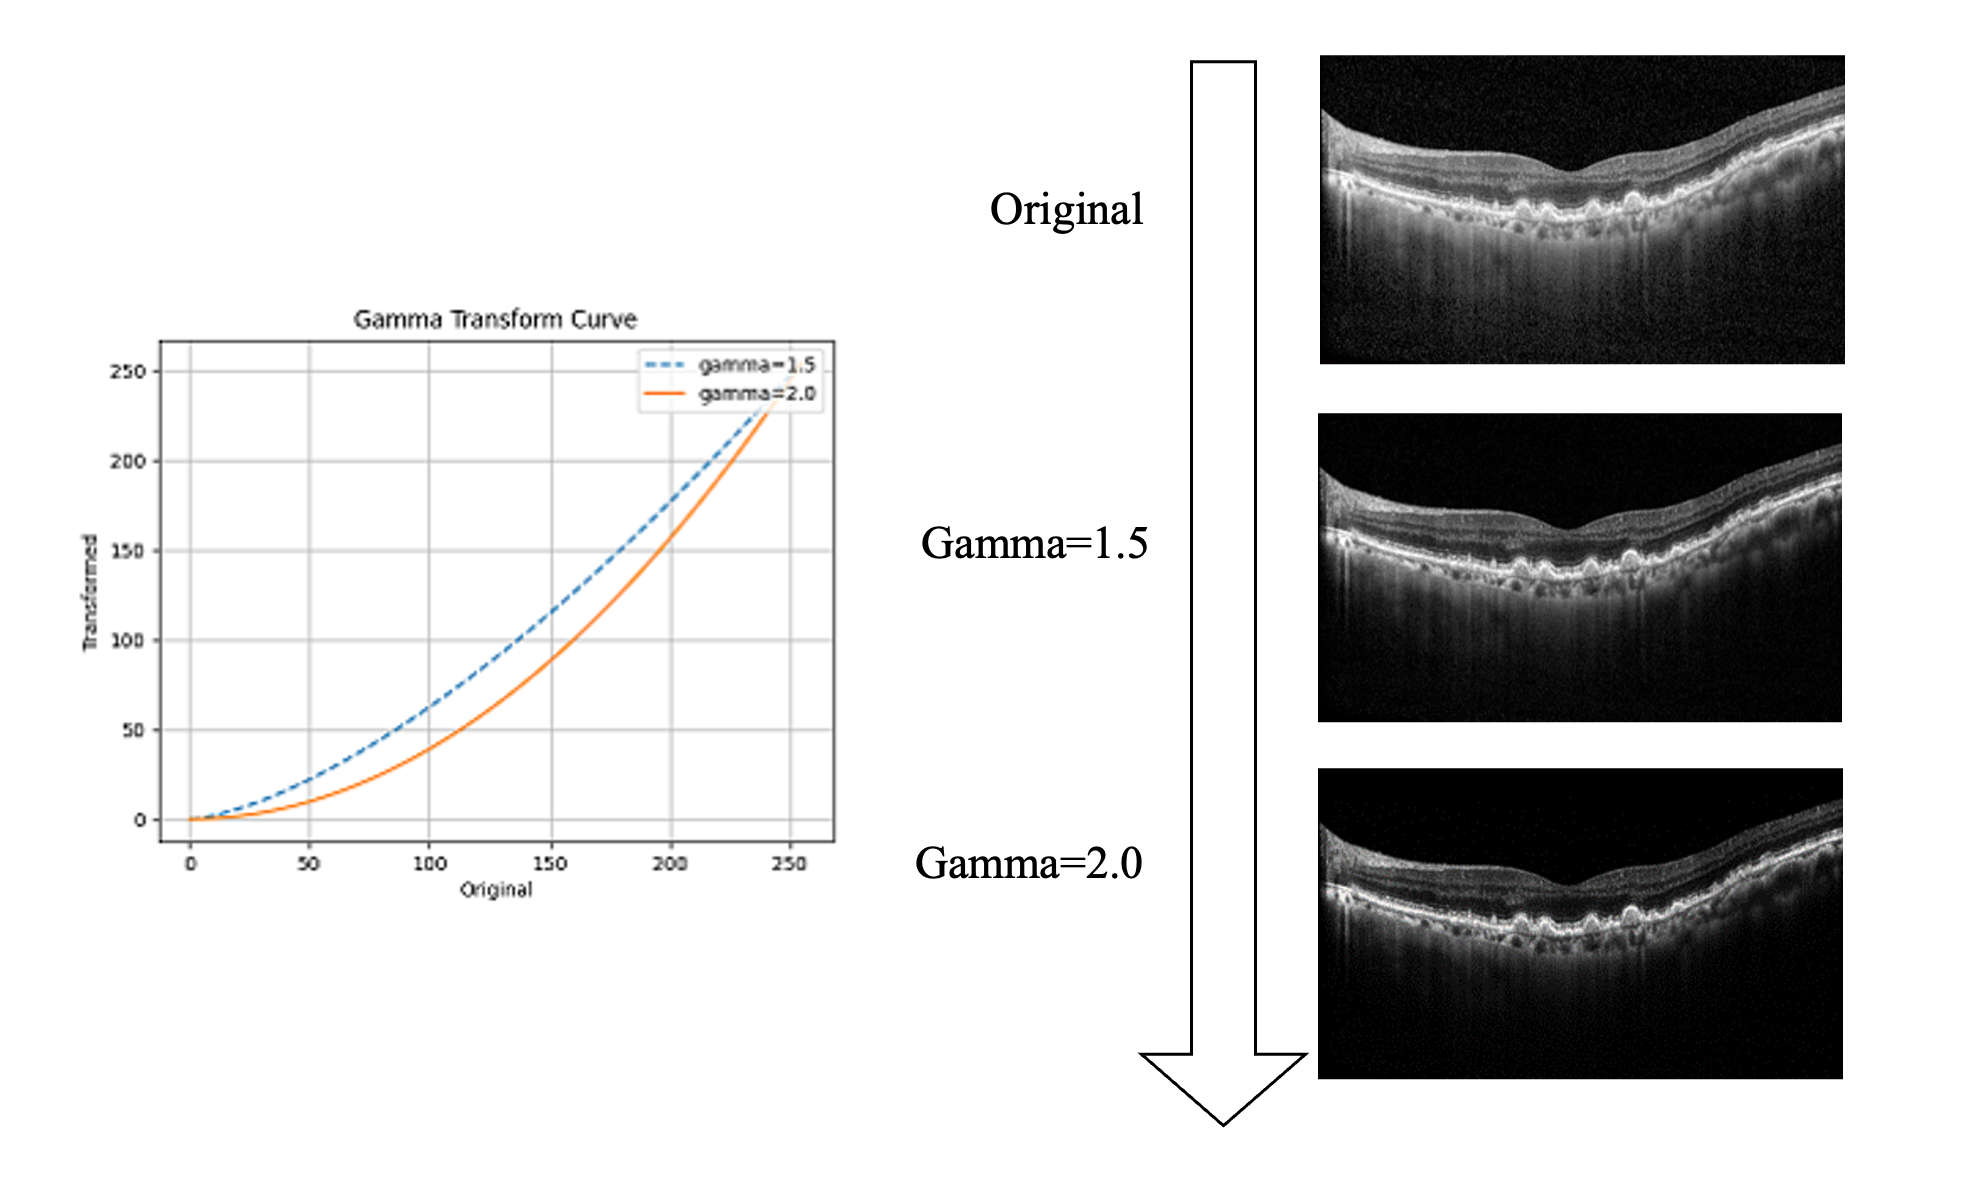

Figure 11: Gama transform of the OCT images.

In the context of predicting PED, the team DarkStyle observed a notable enhancement in the AUC by approximately 0.3% with the application of a gamma transform. The gamma transform, characterized by a transform coefficient greater than 1.0, accentuates dark pixels while dimming light pixels, as illustrated in Figure 11. This improvement can be attributed to that PED symptoms predominantly manifest in the bottom-lightest part of the retina. By applying the gamma transform, these subtle features become more distinguishable, facilitating more accurate identification of PED.